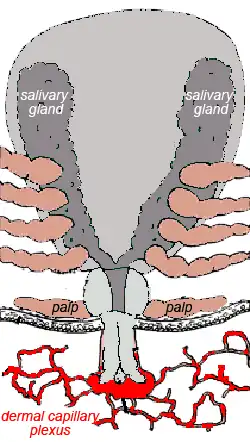

Feeding process

Ticks generally are obligate blood feeders. Active stages (larvae, nymphs and adults) of Ixodes holocyclus require blood as a source of nutrition. Adults also require the blood for sperm or egg production. The feeding process of ixodid ticks has first a slow phase for several days followed by a fast phase in the last 12–24 hours before detachment. There may be a tenfold increase in fed versus unfed weights by the end of the slow phase, but there is another tenfold increase by the end of the final fast phase. Leaving the full engorgement as late as possible reduces the chances of detection and removal by the host. The hypostome has a groove along its dorsal surface forming a food canal (also known as the preoral canal) through which blood is drawn from the host and passed on to the mouth and pharynx. During blood feeding by ixodid ticks, the liquid portion of the meal is first concentrated by removal of water and excess ions, which move across the gut epithelium and enter the tick's body cavity (hemocoele). These components are then taken up by the salivary glands, which produce a watery saliva that is injected back into the host.[24]

Once it has chosen a feeding site, a tick positions itself with its legs so as to elevate its body at a sharp angle. Guided by the palps, the chelicerae cut into the skin with their horizontal cutting action. These rip and tear at the epidermal layers and a small pool of blood is formed. The hypostome is inserted, and this provides the initial attachment strength. In the case of Ixodes holocyclus, the hypostome is inserted very deep into the dermis. The process by which such ticks feed is termed telmophagy (pool feeding). (This contrasts with the process of solenophagy, used by mosquitoes, in which feeding is direct from a small venule.) The resultant pool expands as a result of the anticoagulants released from the salivary glands.[25]

The host reacts against the tick lesion by haemostasis, inflammation and cell-mediated immunity. An array of pharmacologically active substances is injected with the saliva of the tick, including anticoagulants, prostaglandin E2, prostacyclin, apyrase and, in certain tick species, antihistamines. Prostaglandin E2 and prostacyclin inhibit platelet aggregation and dilate blood vessels. Feeding is almost continuous, with pulses of salivation alternating with periods of feeding to ensure continued suppression of host defences.

There is a concentration of saliva and presumably toxin in the granulomatous reaction around the tick mouth parts. It is thought by some experimenters that the residual toxin located in this granuloma is at least partially responsible for the increasing paralysis which occurs after the tick is removed. By comparison, the North American paralysis tick Dermacentor andersoni (found in the Rocky Mtns) does not produce a granuloma at the site of attachment, and in this case the paralysis rapidly regresses after the tick is removed.[20] Unlike Dermacentor andersoni, Ixodes holocyclus is a deep feeder with a long hypostome (which may penetrate as deep as 1689 um).

Pets

Dogs and cats on the east coast of Australia commonly succumb to the tick paralysis caused by Ixodes holocyclus. A similar tick species, Ixodes cornuatus, appears to cause paralysis in Tasmania.[58] The paralyzing toxin (or toxins) is produced in the salivary glands and injected as part of the feeding process.